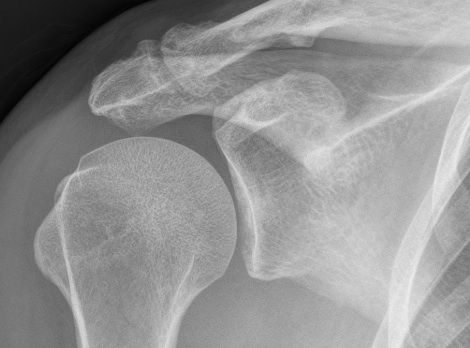

1. Osteoarthritis with osteophytes

Visible deformity / swelling / osteophytes

Xray

Zanca view - AP 10° cephalic tilt with 50% penetration